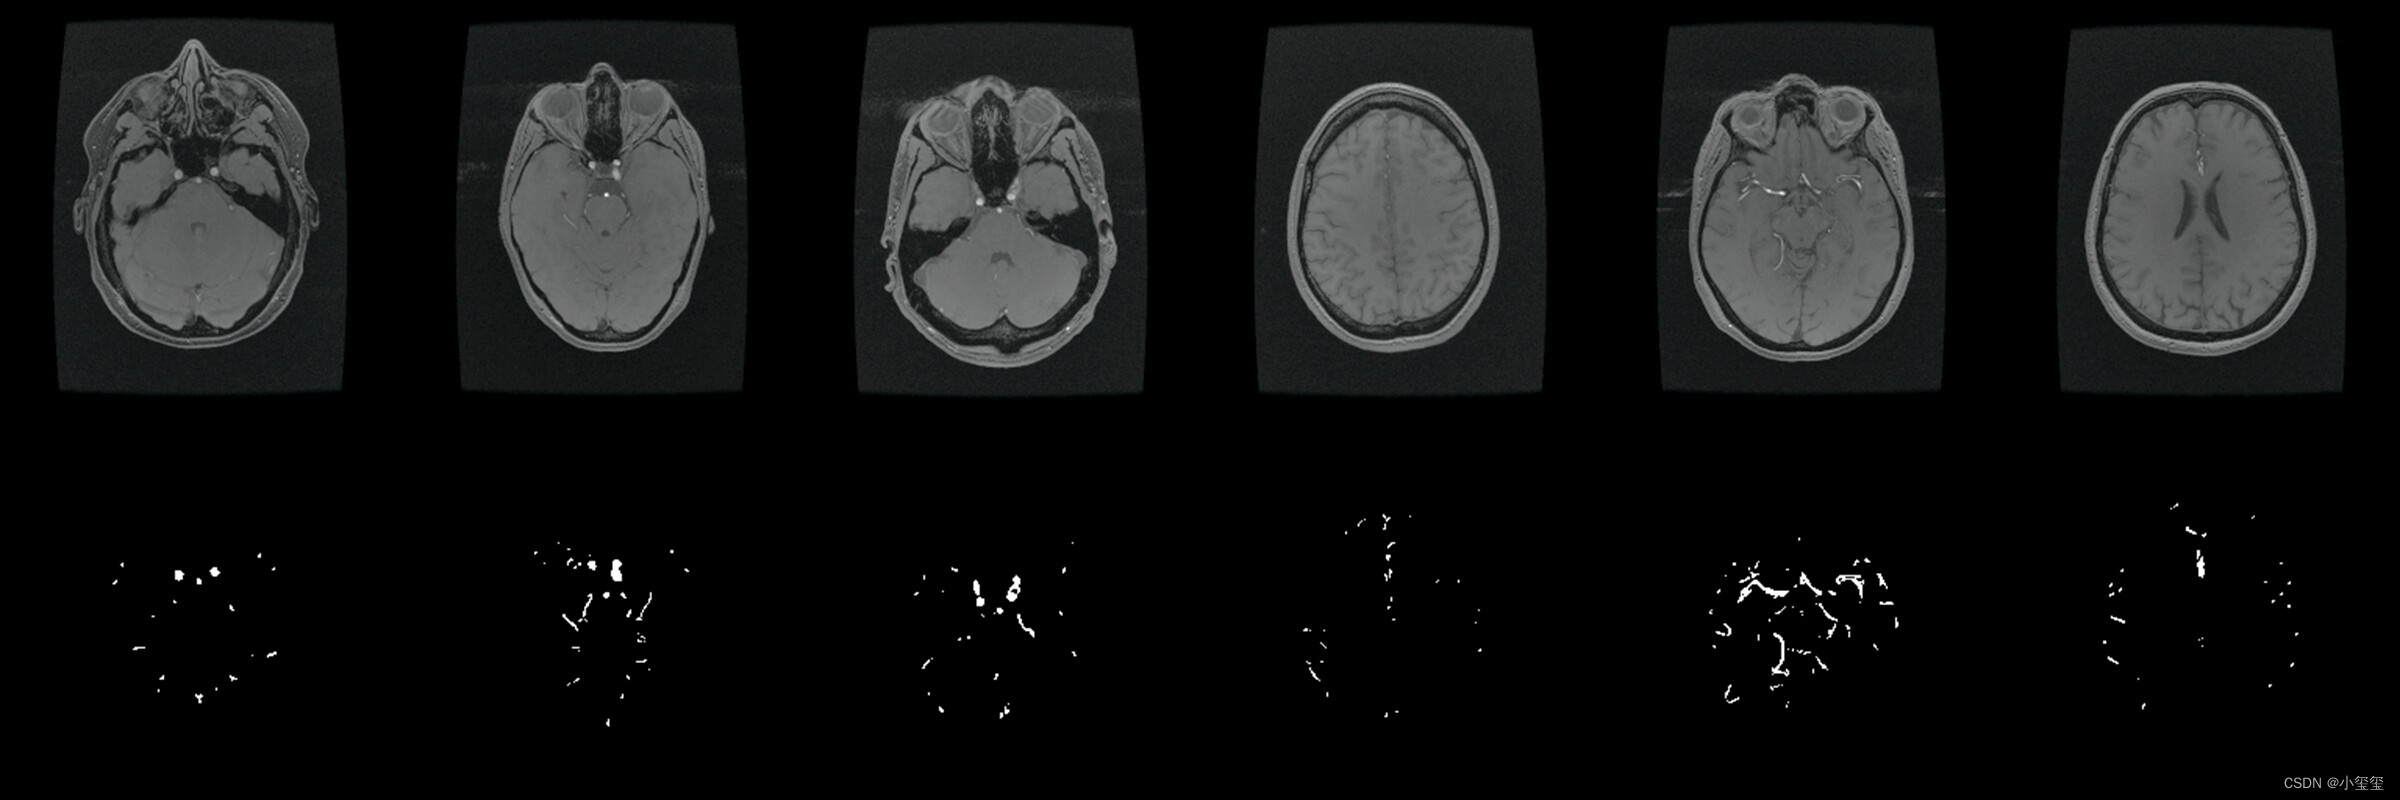

整个流程的演示我以医疗应用为背景,基于UNet完成训练、量化、部署整个流程。PS:之前想以细胞分割来展示,但是GT视觉效果比较密恐,所以找师弟要了一套看来舒服一点的医疗数据集重新训练更换效果图。

- 数据集来自2022年发表在TMI的论文《Attention-Assisted Adversarial Model for Cerebrovascular Segmentation in 3D TOF-MRA Volumes》。数据集实际上是MRA图像,我这里只保留了脑血管GT,用二分类的Unet来介绍整体的部署流程(这里感谢诺师弟的帮助)。

执行完代码之后,得到ONNX结果,看起来没啥问题,可以进行阶段2的相关数据转换了。